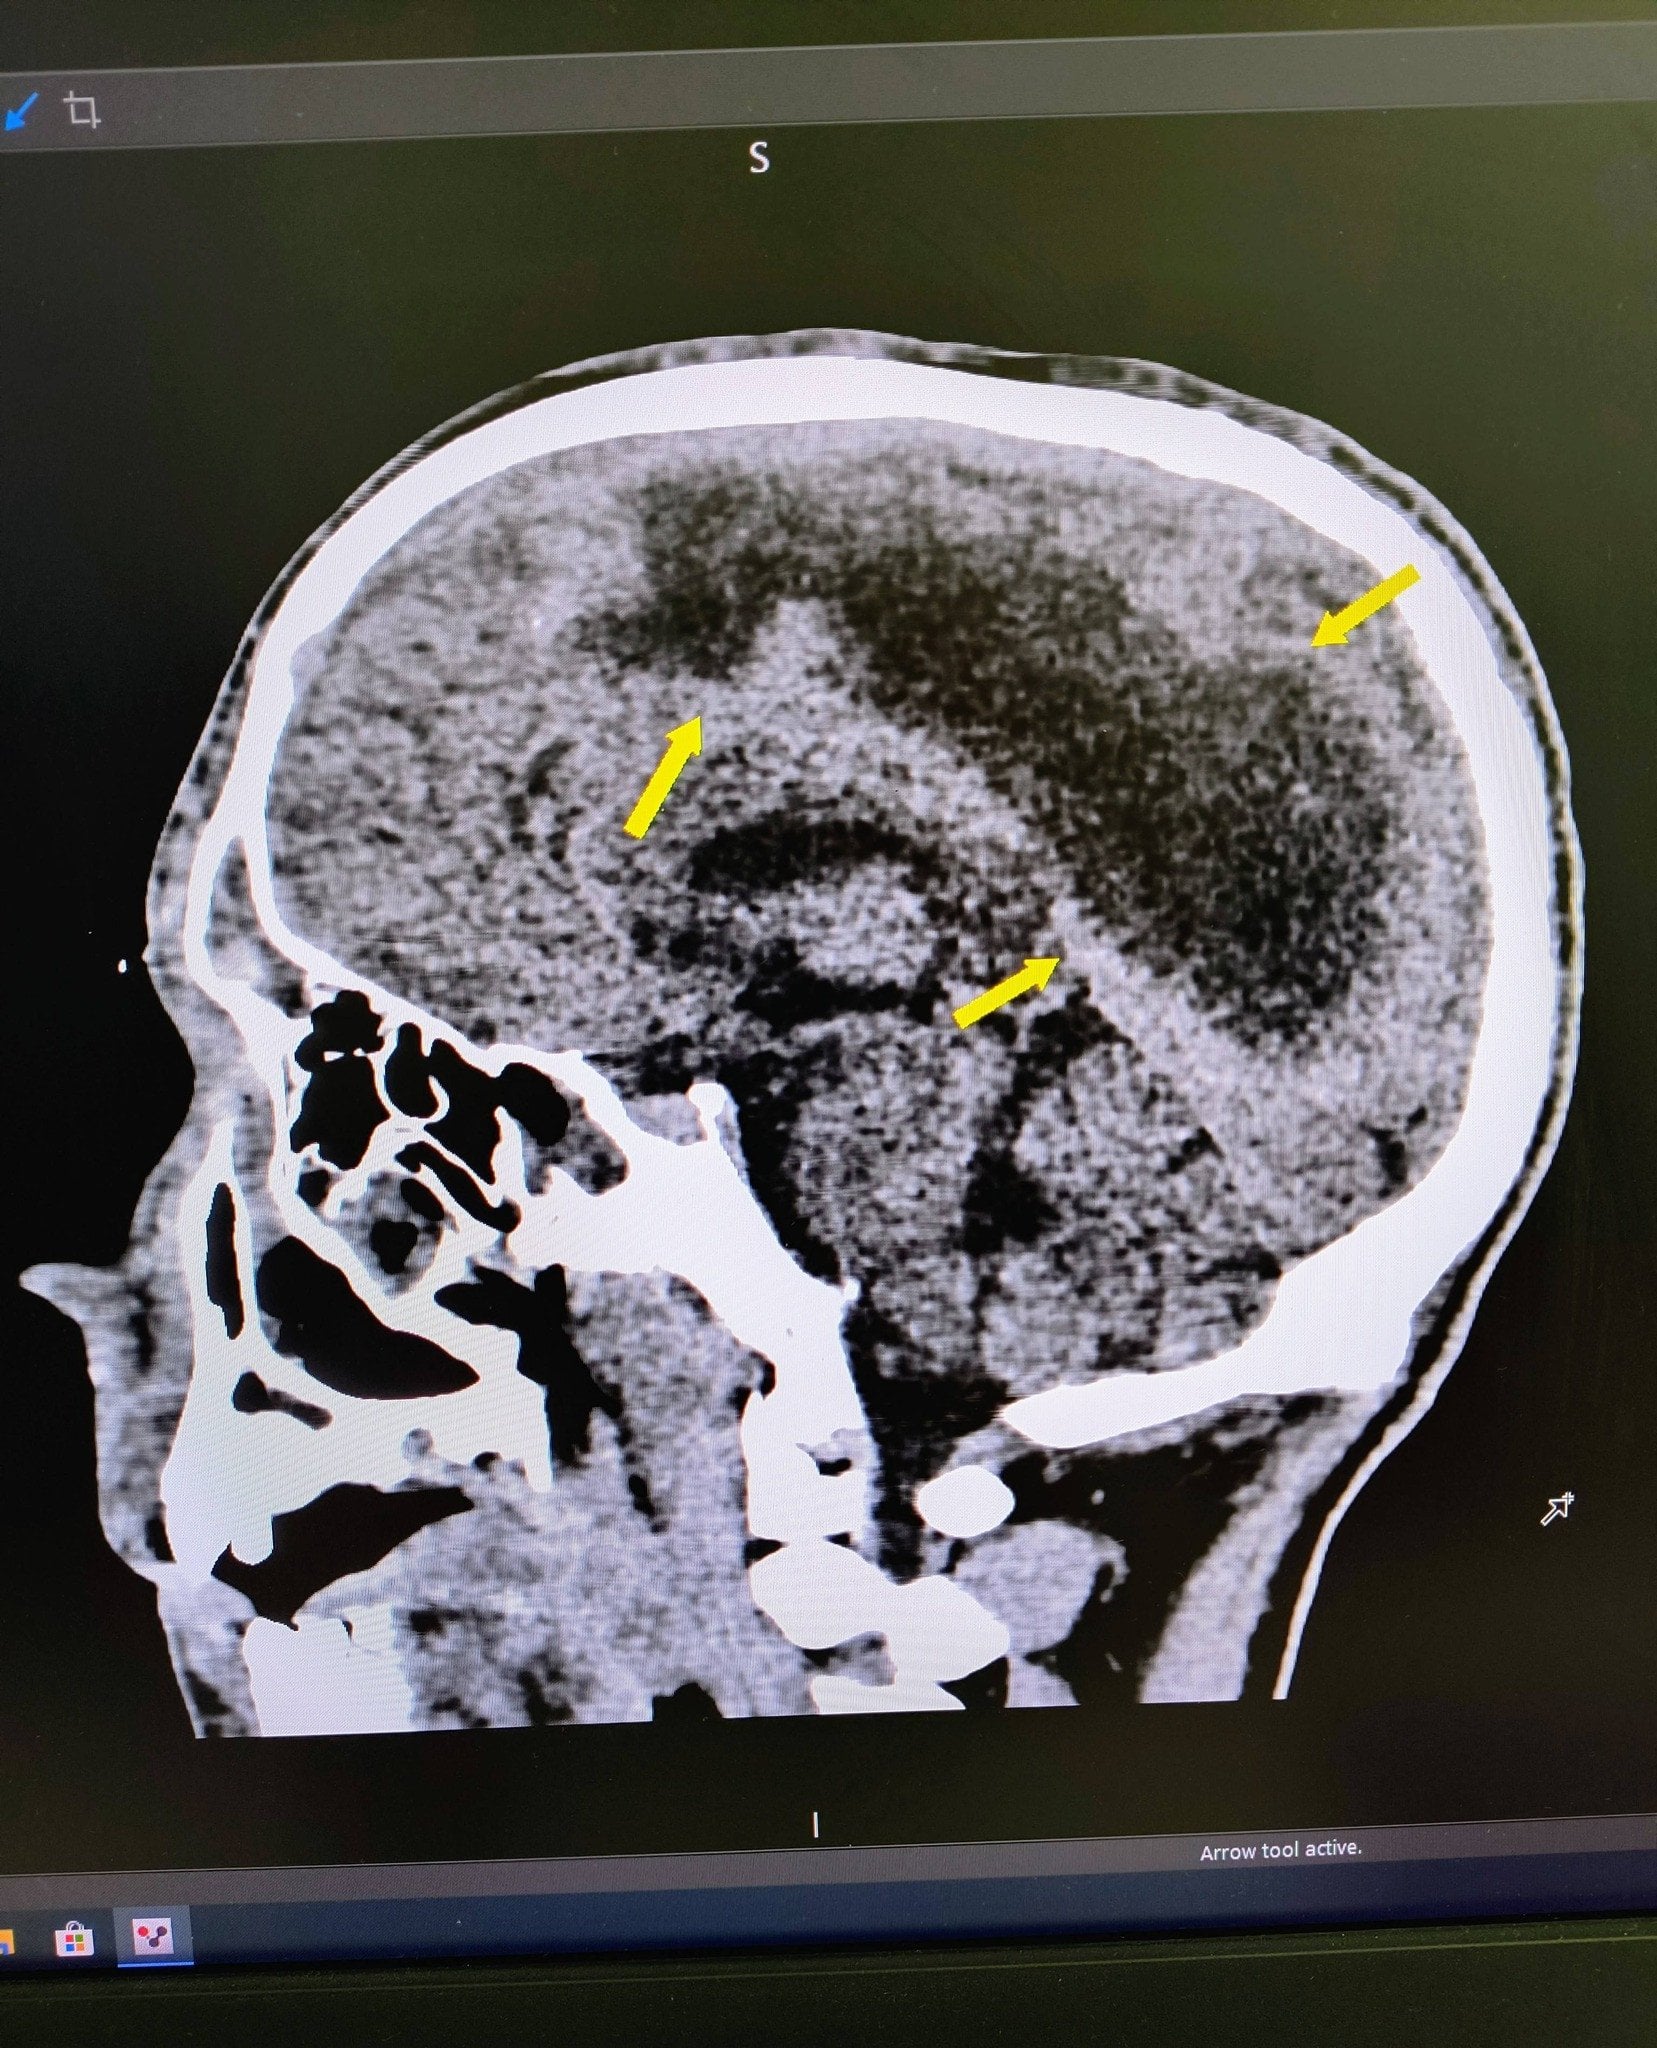

«Пацієнт поступив до нас у стані глибокої коми. За даними КТ в дитини була емпієма, тобто масивне скупчення гною над правою півкулею головного мозку. Ми провели оперативне втручання, дренувавши вміст емпієми, тобто забрали гній з мозку», — розповів нейрохірург лікарні Святого Миколая Юрій Кузьмінський.

Дослідження причин критичного стану показало, що все почалося зі звичайного синуситу — запалення приносових пазух, яке виникло як ускладнення після застуди. Через порушення відтоку слизу утворився гній, що поширився у мозок та очні ямки.